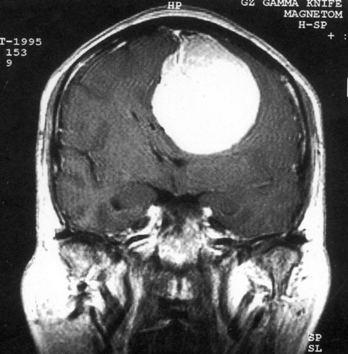

问题 病历摘要:??患者女性,37岁。大便时突起炸裂样头痛3小时,伴喷射样呕吐。既往体健。体检:T37.5℃,BP145/90mmHg,R20次/分,P85次/分。神志清楚,颅神经检查无异常,颈强直,克、布氏征(-),四肢肌力、肌张力正常,病理征(-)。 目前一般认为颅内动脉瘤形成的病因主要有哪些?提示:入院后?10小时行DSA检查,发现前交通动脉瘤